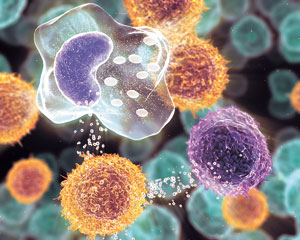

문제는 체내 어느 곳에서 염증이 발생하면 다양한 염증 관련 화학물질이 온 몸으로 이동해 전혀 다른 곳의 장기에도 영향을 미친다는 것. 특히 특정 부위의 염증반응이 다른 부위의 암을 일으킬 수도 있다는 새로운 개념이 등장했다.

미국 MIT대 디돈 박사는 논문을 통해 몸 어딘가에서 감염이 일어나면 외부 침입자와 싸우기 위해 대량으로 분비되는 화학물질인 사이토카인과 관련 효소 등이 정상 세포들의 DNA 구조에 손상을 일으켜 암을 유발한다고 발표했다.

사이토카인은 세포에서 분비돼 세포 간 신호 전달, 세포의 행동 조절, 면역반응 조절 등에 관여하는 생물활성인자를 일컫는 말이며, 인터류킨'림포카인'인터페론'세포증식과 분화인자 등 저분자 단백질을 뜻한다. 백혈구에서 만들어지는 인터류킨은 세균이나 해로운 물질을 면역계가 맞서 싸우도록 자극하는 단백질이다. 상처에 세균이 침입하면 특정 백혈구가 세균을 알아채고 인터류킨을 방출하고, 인터류킨은 백혈구의 일종인 T세포를 활성화시켜서 세균을 파괴하도록 한다.